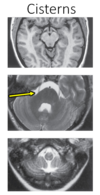

•Recall the material covered in Gross Anatomy concerning circulation, CSF and meninges. •Identify the components of the ventricular system and adjacent brain structures. •Identify the cisterns around the brain in brain slices or MRI/CT images. •Compare the composition of CSF to blood. •List the general functions of the structures that surround the ventricles. (82 cards)